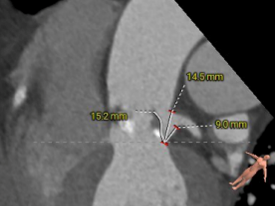

CT测量

主动脉根部CT测量

瓣环周长:90.3mm

LVOT周长:97.1mm

瓣环上4mm:82.7mm

瓣环上6mm:85.6mm

左冠开口高度:21.4mm

右冠开口高度:16.3mm

左窦瓣叶长度:20.8mm

右窦瓣叶长度:19.1mm

STJ周长:129.8mm

升主动脉周长:157.5mm

法氏窦

周长:133.9mm;左冠状窦直径:45.4mm;无冠状窦直径:31.8mm

主动脉瓣钙化积分:787mm2

左冠开口高度:7.1mm

右冠开口高度:13.7mm

左窦瓣叶长度:15.2mm

右窦瓣叶长度:16.6mm